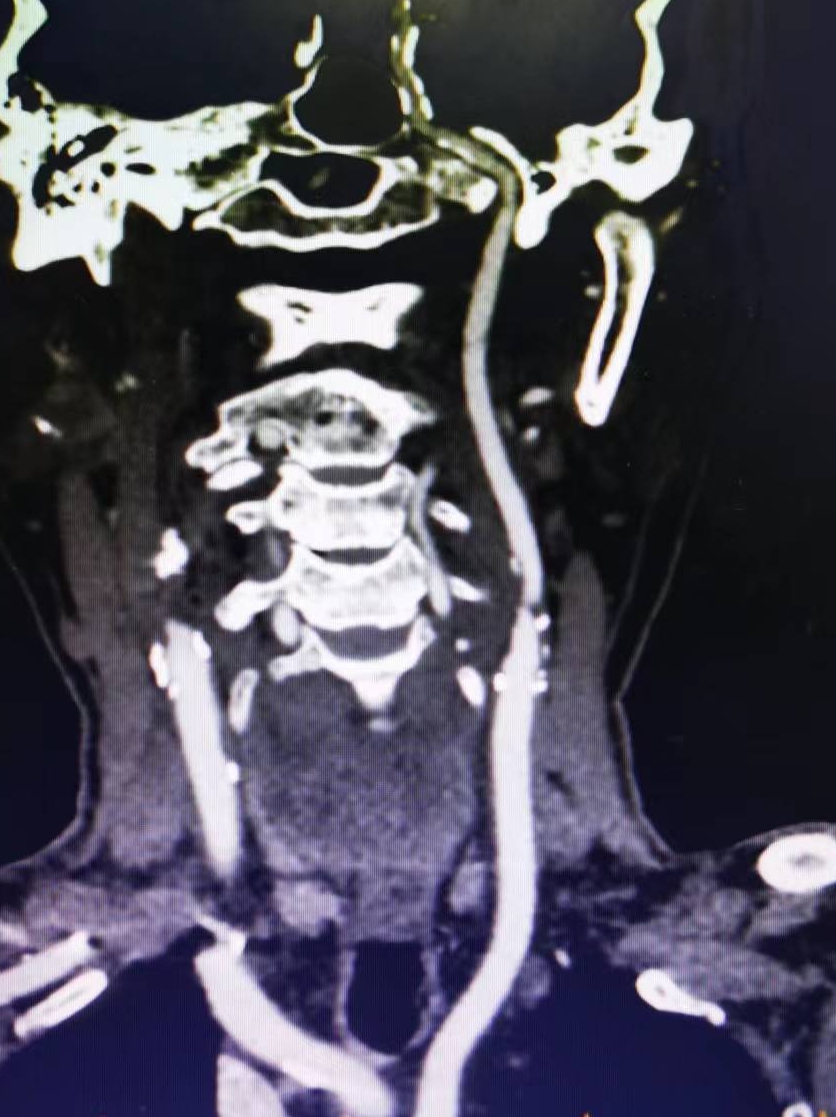

患者男性,70岁,体检发现双侧颈内动脉重度狭窄,1月前行右侧颈内动脉支架成形术,现为治疗左侧颈内动脉狭窄入院。既往高血压病史30年,口服硝苯地平控释片降压,血压控制130/80mmHg。

2、左侧颈内动脉从CTA看狭窄合并软斑,具备介入治疗指征。